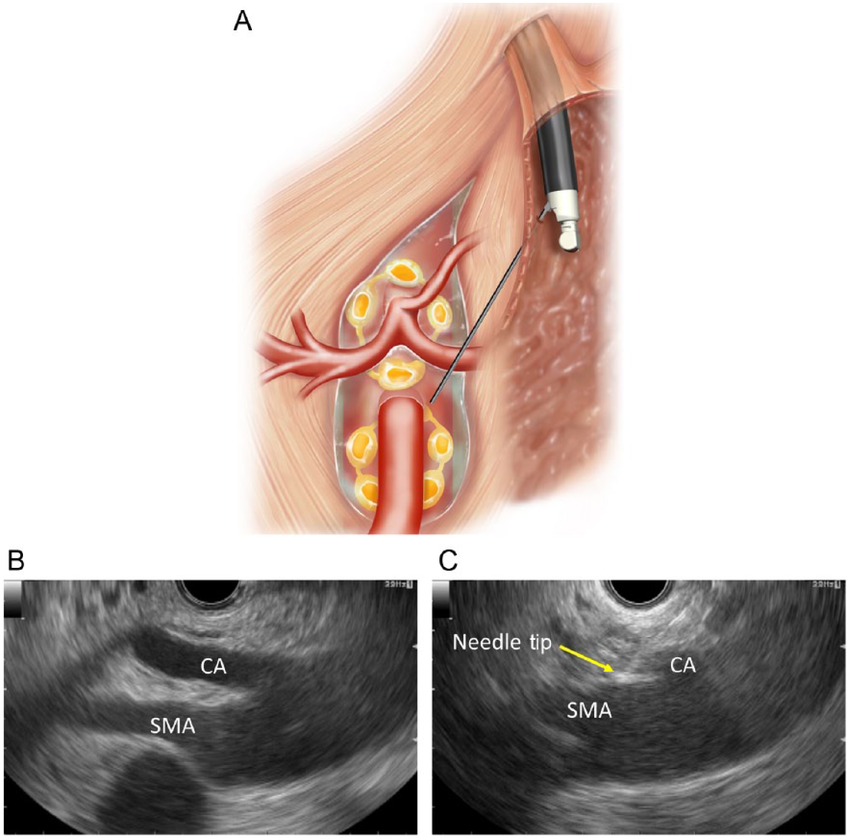

EUS uses a flexible tube with an ultrasound probe at its tip, introduced through the mouth or rectum, to generate high-resolution images of internal organs. Unlike external scans, EUS provides closer and clearer views of the digestive tract and nearby structures.

• ๐Ÿ” Enables tissue sampling using a fine needle

• ๐ŸŸข Celiac plexus neurolysis for pain relief in cancer

• ๐Ÿ“ก Real-time ultrasound imaging used to guide the procedure

• ๐Ÿงซ Biopsy or therapy performed if needed